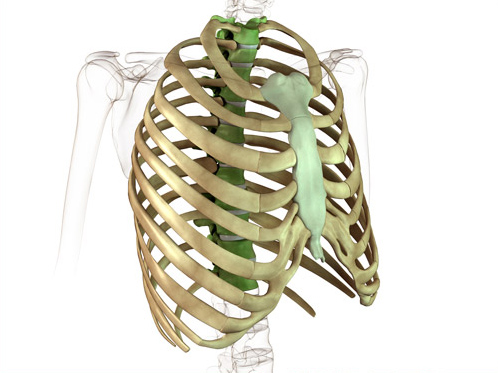

このセッションでは膀胱経についてお話しします。膀胱経は頭の後ろから背中そして股裏を通って最後は小指までついている経絡です。背部の脊椎の左右を流れているため、その部の経穴は、自律神経を介して、様々な臓器に影響を与えています。人体が冷えたり熱をもったりしないでバランスが取れた健康な状態を保つためには、この膀胱経が不可欠となっています。

膀胱経をより効果的に流れを良くするためには、仙骨周囲の気門を開くことがポイントになります。イメージとしては、この場所に穴を開けるようにと意識しながらおこなうことで、気門が開きやすくなり、次に経穴を治療するときにより効果を発揮します。

ここでお伝えするのは、承扶(しょうふ)というポイントです。この経穴は臀部と大腿の境にあるお尻の溝の中央にあります。また、この場所は坐骨神経の走行する場所であり、解剖学的にも滞りやすい場所なのです。

頭の後ろから背中そして太ももの裏を通って最後は小指まで走行しています。このセッションでは気門・経穴と流れを良くしたところで、最後にこの経絡使った治療をやるからこそ、効果は3倍で誰にでもできるテクニックになっております。